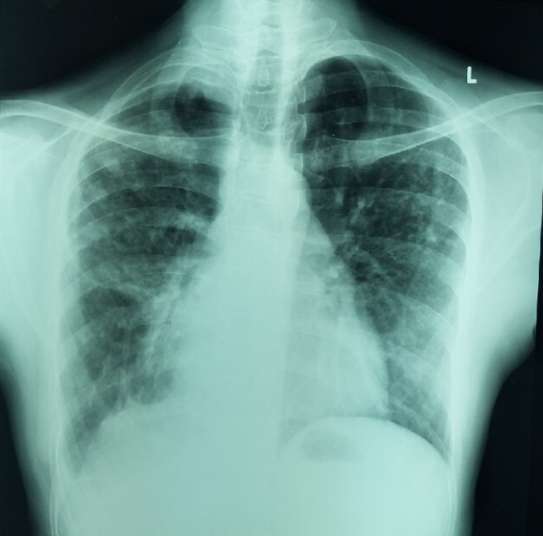

폐결절 원인부터 증상, 통증, 폐암 확률까지의 진실을 아시나요?

폐결절 원인부터 증상, 통증, 폐암 확률

이번 포스트에서는 폐결절 원인부터 증상, 통증, 예방법, 좋은 음식, 폐암 확률까지의 내용을 정리해 보았습니다. 증상을 앓고 계시거나, 예방을 위한 모든 분들에게 도움이 되기를 바라겠습니다. 폐결절에 대하여 폐결절은 폐조직 내에서 발견되는 약 3cm 미만의 작은 결절이며 대개 양성 종양입니다. 폐 결절은 증상 없이 발견되는 경우가 많고, 일부 사례는 천천히 진행되는 폐암의 초기 단계가 될 수도 있습니다. … 더 읽기